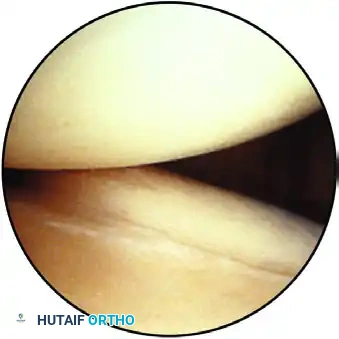

The inferior pouch, displaying the hammock-like structure of the glenohumeral ligaments and the inferior labrum.

As the arthroscope enters the inferior pouch, the lens is rotated back toward the superior glenoid. Evidence of instability—such as synovitis, loose bodies, or labral detachment—is noted.

Capsular attachment to the humeral head, observed through the inferior pouch.

Using a probe from the anterior portal, the humeral head is gently lifted from the glenoid to stress the capsulolabral attachments.